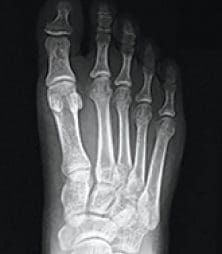

Bunions are more than a simple bump on the side of the foot — they are complex, three-dimensional deformities caused by an unstable joint at the base of the big toe. While many people assume a bunion can simply be “shaved off,” traditional procedures often fail to correct the true source of the problem. This is why bunions commonly return, leaving nearly 1 in 3 patients dissatisfied with prior surgical results.

Lapiplasty® 3D Bunion Correction™ is a patented, cutting-edge procedure designed to correct the full 3-dimensional deformity rather than just removing the bump. By addressing the unstable joint and restoring the bone to its proper anatomical position, this procedure provides a more stable, lasting correction with faster recovery and improved function.